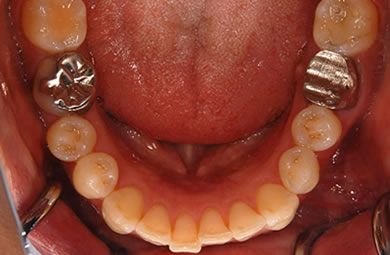

インプラントの症例写真 IMPLANT

インプラント治療+セラミック治療

| 治療方針 | 前歯部の審美的回復をセラミック治療で行う。臼歯部の審美的・機能的回復をインプラント治療で行う。 | ||||||||||||||||||||||||||||||||

| 治療内容 | インプラント1本、メタルボンドセラミック1本、オールセラミック2本(オールセラミック用の土台2本) | ||||||||||||||||||||||||||||||||

| 総治療費 | 608,667円 | ||||||||||||||||||||||||||||||||

| 治療期間 | 4ヶ月 |